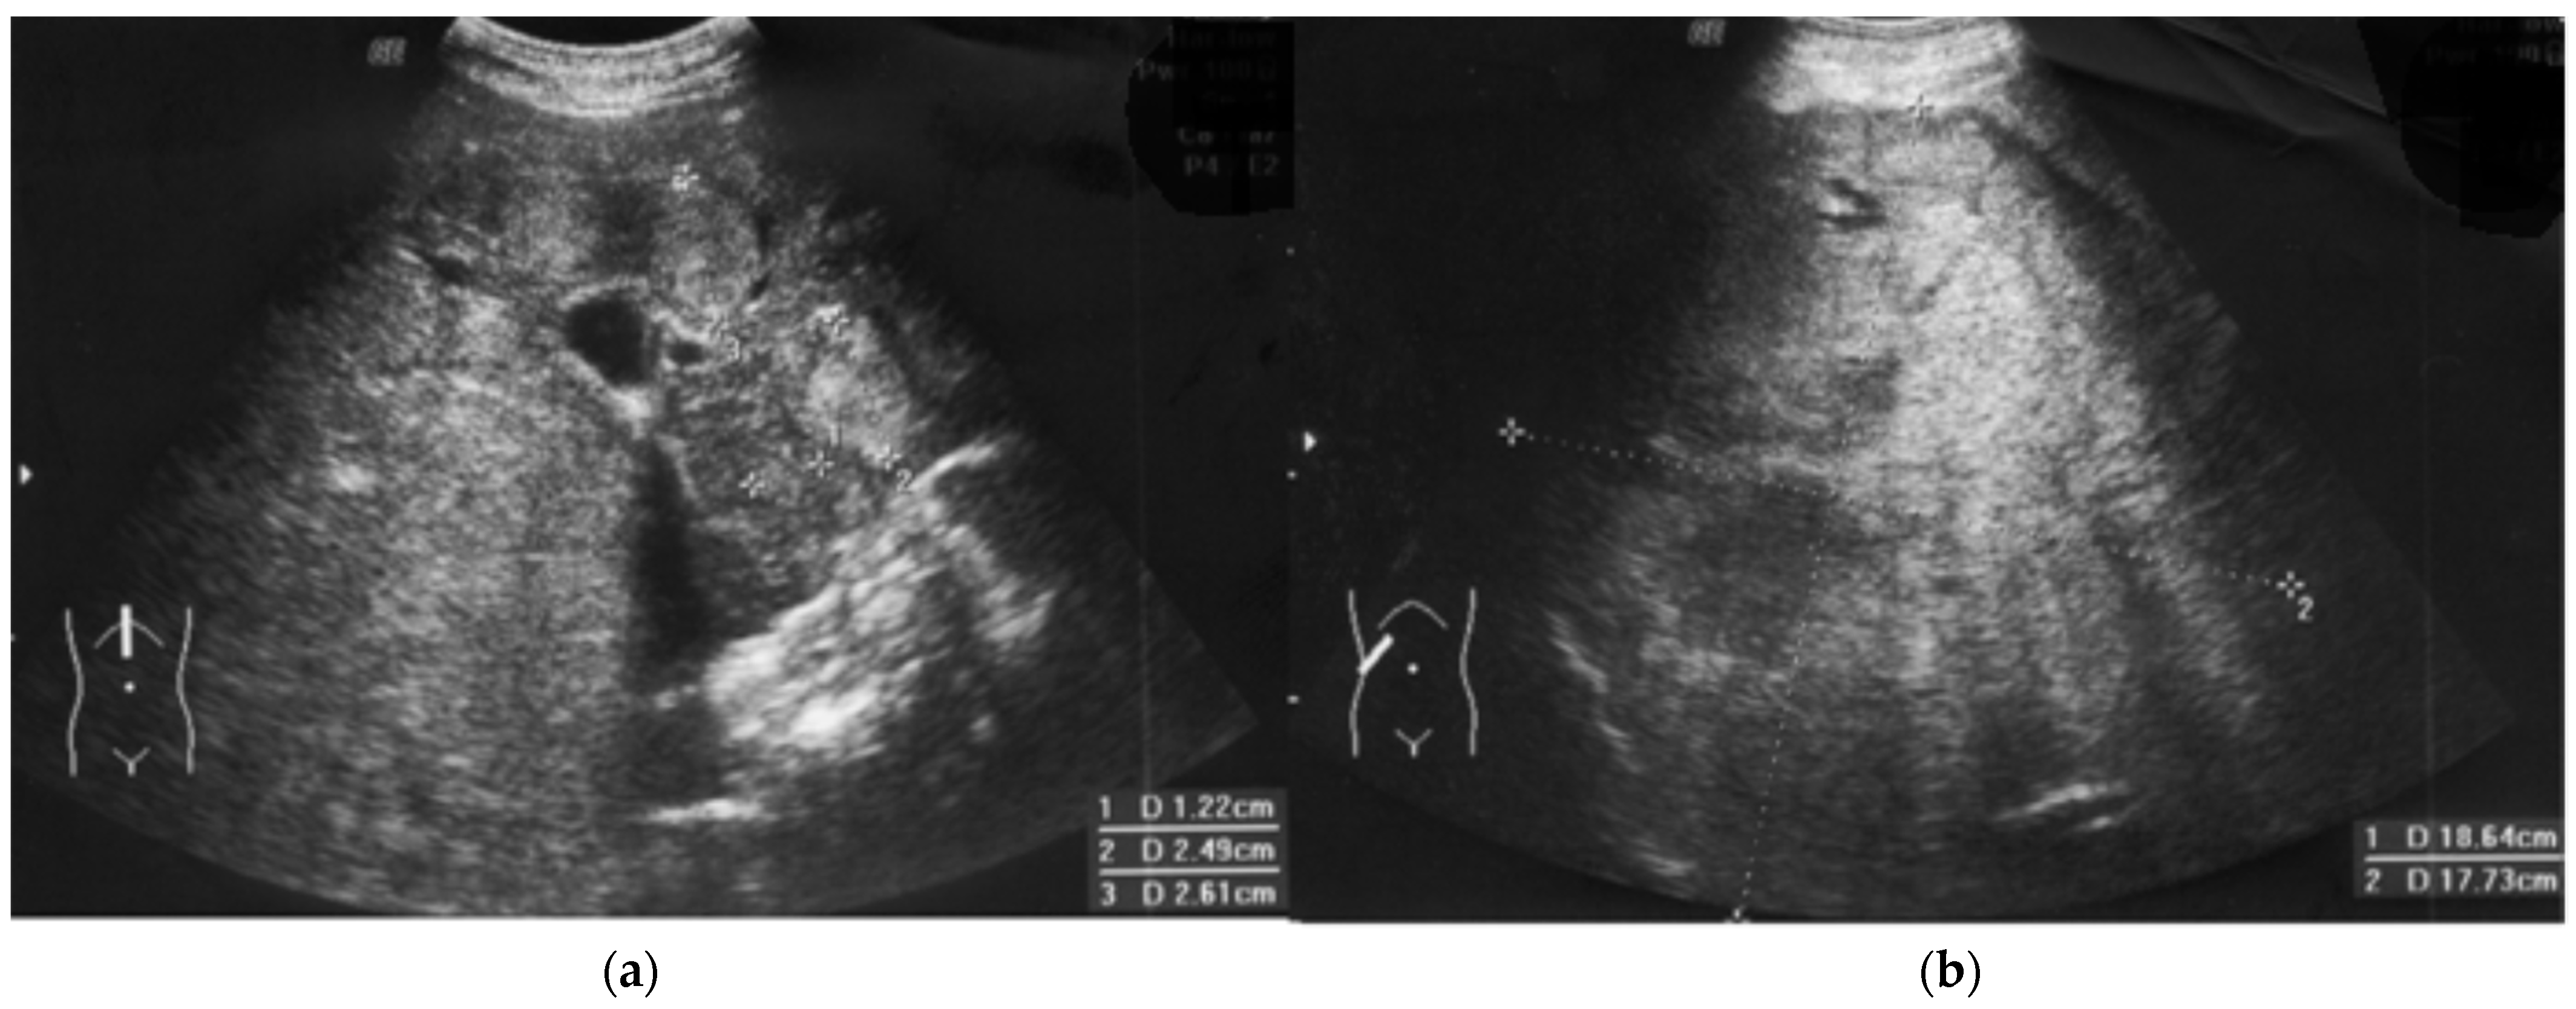

Suddenly and unexpectedly, the patient developed the following symptoms: muscle and joint pain, general weakness, lack of appetite, nausea and vomiting, and stomach pain. No jaundice was observed, and ALAT and bilirubin levels were normal. The family doctor recognized an intestinal infection. The patient received symptomatic treatment and diet. Microbiological tests were negative, but pruritus occurred. At the follow-up visit prior to subsequent IVIG substitution, the patient reported discolored stool and pain in the right hypochondrium (Figure 1, September). HBs antigen levels before substitution were positive, but the liver function test results were all normal (ALT = 33U/L, AST = 30 U/L). The pre-emptive lamivudine therapy [14], time-lapse analysis of anti-HBs, HBsAg, and complements C3 and C4 were introduced (Figure 1). He received 300 mg/d of lamivudine in divided doses. The level of HBV-DNA by polymerase chain reaction (PCR) was also examined. Real-time PCR showed extreme levels of viral load (61,500,000 IU/mL, i.e., 369 × 106 copies). Opportunistic viruses (e.g., cytomegalovirus, Epstein–Barr virus) were negative, and HCV and HIV RNA were not detected. HDV-specific antibodies (class IgM and IgG) were negative during observation. Due to a significant decrease in the IgG level before the next substitution, the dose of IVIG was increased, although anti-HB levels were still high (Figure 1). Despite lamivudine therapy, lack of jaundice, rapid changes in mental status, or unexplained bleeding, the ultrasound image showed heterogeneous nodules (1.2–3 cm, see Figure 2a, i.e., from January).

Figure 2.

Fulminant hepatocellular carcinoma HCC progression in a patient with immunodeficiency. Regularly (every 3 months) performed ultrasound examinations (liver, spleen, lymph nodes) did not show any changes in October, but the ultrasound image showed heterogenous nodules (January), (a) that resemble nodular regenerative hyperplasia, typical for CVID [2]. The first blind liver biopsy (January) was non-diagnostic. Afterwards, a 110 mm tumor developed, and HCC was confirmed by second biopsy (April). Finally, fulminant growth up to 180 mm was observed despite lamivudine therapy, vaccination, normal ALT, and high anti-HBs level (b).

The patient had progressive resistant thrombocytopenia (till 30–40 × 103/μL) and coagulopathy (see below). At this stage (February), the patient was not qualified for surgery. Due to B cells < 1%, there was no target for rituximab. IVIG dose was increased for the treatment of thrombocytopenia in CVID [2] (Figure 1). Further on, computer tomography showed 11 cm intrahepatic tumor; afterwards, hepatocellular carcinoma and hepatic cirrhosis were confirmed by core needle biopsy. The first biopsy (January) was non-diagnostic and showed no significant abnormalities, whereas the second (April) (in stage IIIA-IVB HCC) was representative.

In the initial stage of HCC, nodular changes are similar to nodular regenerative hyperplasia (Figure 2a), treated with rituximab [2]. Malignancy development in patients with primary immunodeficiency requires a different investigative approach to immunotherapy [35].